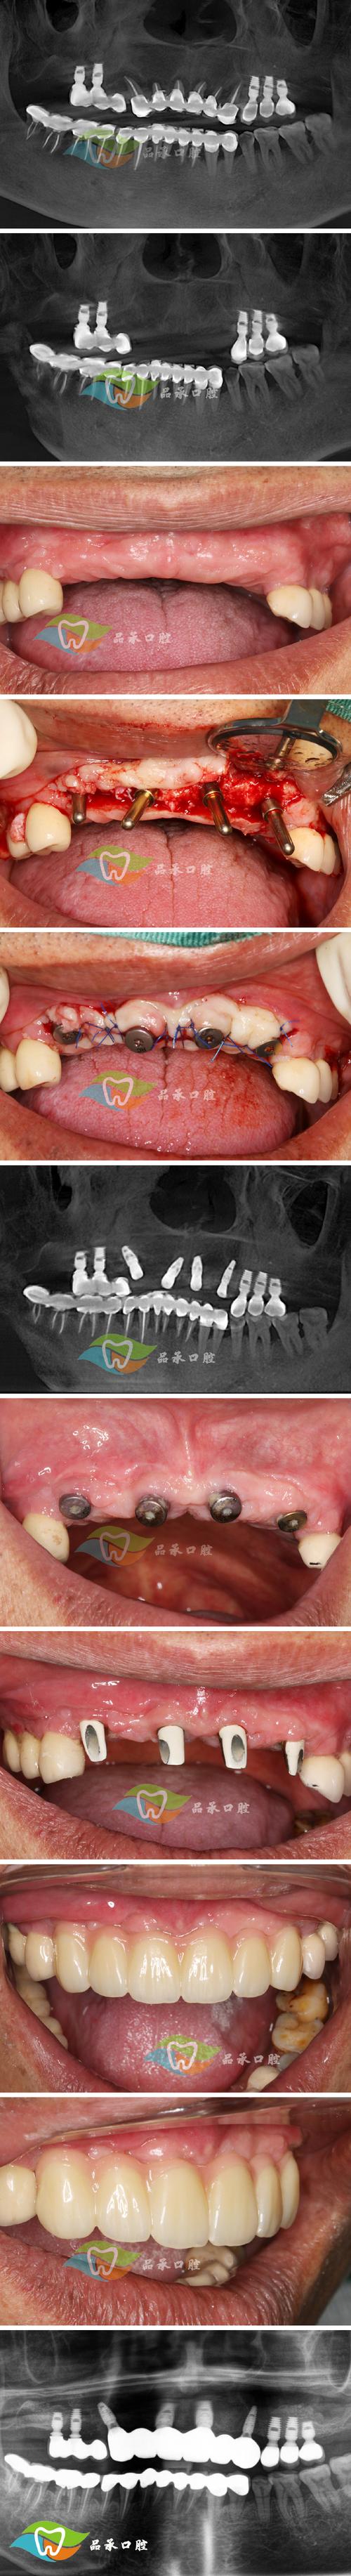

- 临床实践: 在80年代末至90年代初,九院就已经开始为符合条件的患者实施种植牙手术,并积累了宝贵的早期临床经验,这被认为是上海地区最早、最系统、最持续开展种植牙临床实践的机构。

- 系统开展与专科建立: 上海第九人民医院口腔种植科的建立和发展,标志着种植牙技术在上海从零星尝试走向系统化、专科化、规范化,该科室在90年代中后期就已经是国内种植牙领域的标杆,培养了大批人才,制定了行业标准,并持续推动技术进步,说九院是上海种植牙技术的摇篮和发源地是业界公认的。

- 技术背景: 早期主要依赖国际成熟的种植系统(如Branemark系统),由口腔颌面外科和修复科专家团队主导。